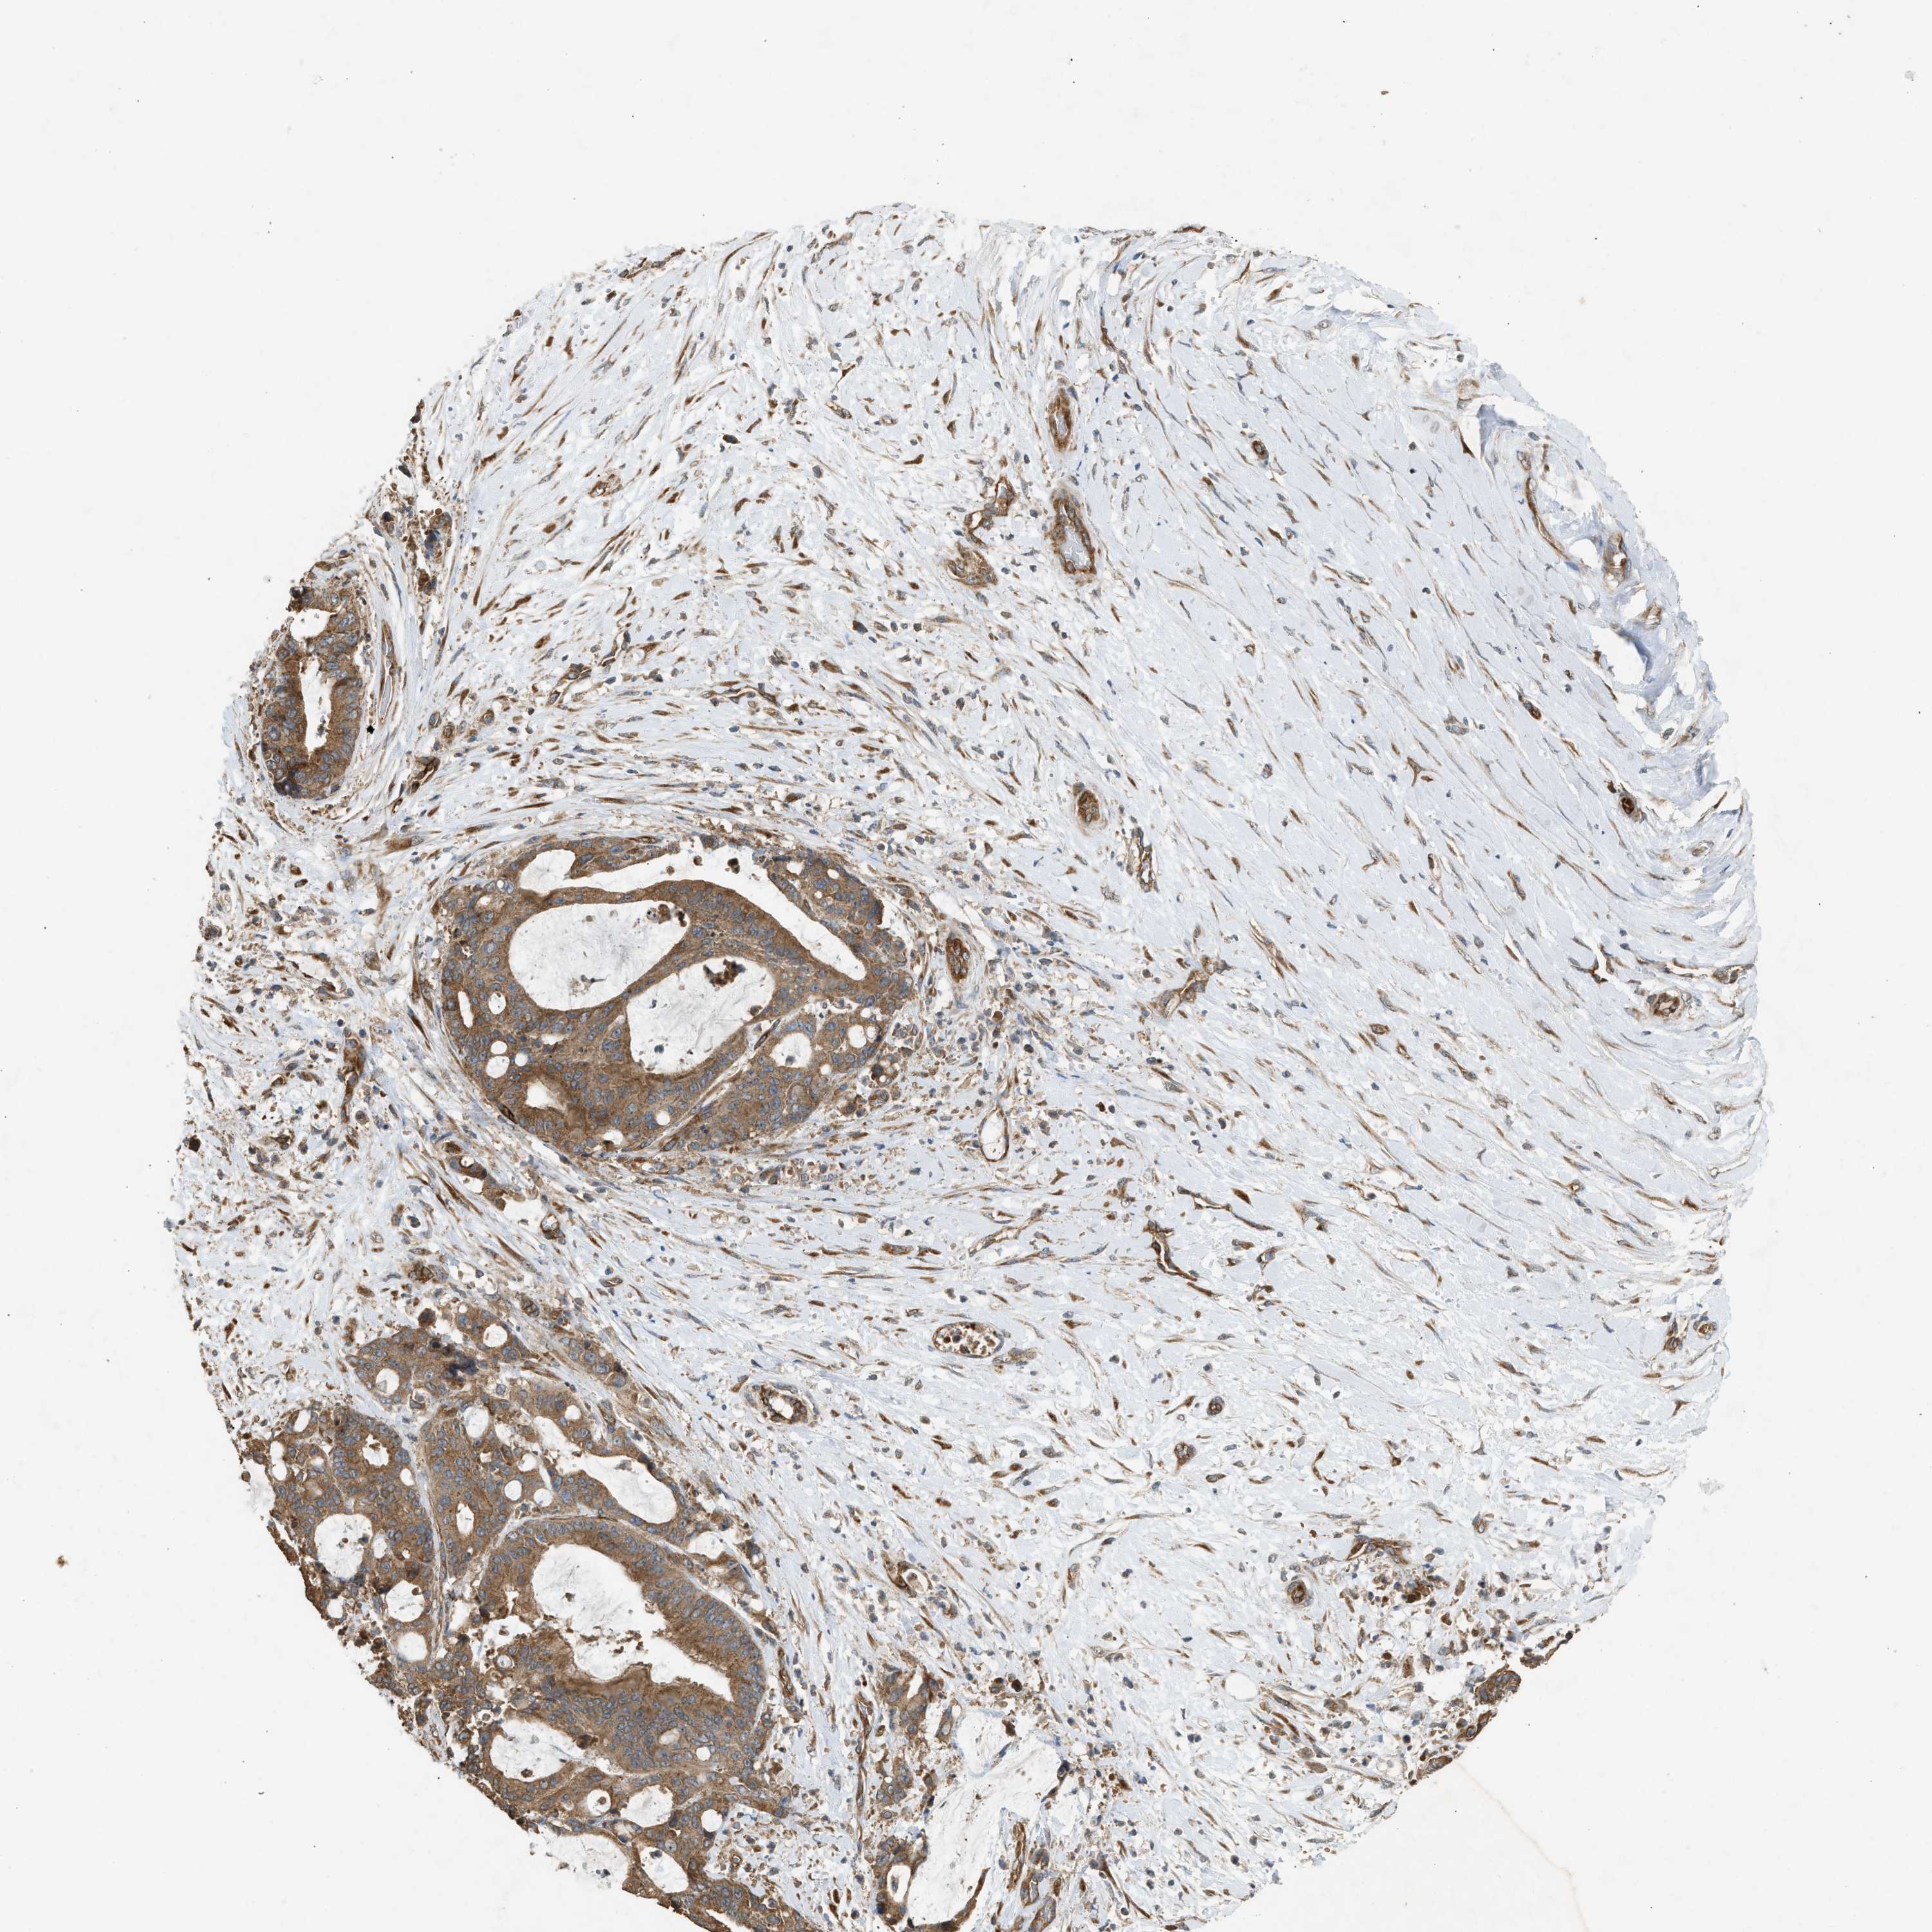

LIVER CANCER - Protein expressioni

A mouse-over function shows sample information and annotation data. Click on an image to view it in a full screen mode. Samples can be filtered based on level of antibody staining by selecting one or several of the following categories: high, medium, low and not detected. The assay and annotation is described here.

Note that samples used for immunohistochemistry by the Human Protein Atlas do not correspond to samples in the TCGA dataset.

Antibody stainingi

Antibody staining in the annotated cell types in the current human tissue is reported as not detected, low, medium, or high, based on conventional immunohistochemistry profiling in selected tissues. This score is based on the combination of the staining intensity and fraction of stained cells.

Each image is clickable and will lead to virtual microscopy that enables deeper exploration of all samples and also displays staining intensity scores, fraction scores and subcellular localization as well as patient and tissue information for each sample.

Antibody HPA038135

Antibody HPA038136

Antibody CAB017187

Staining

Cholangiocarcinoma

Carcinoma, Hepatocellular, NOS